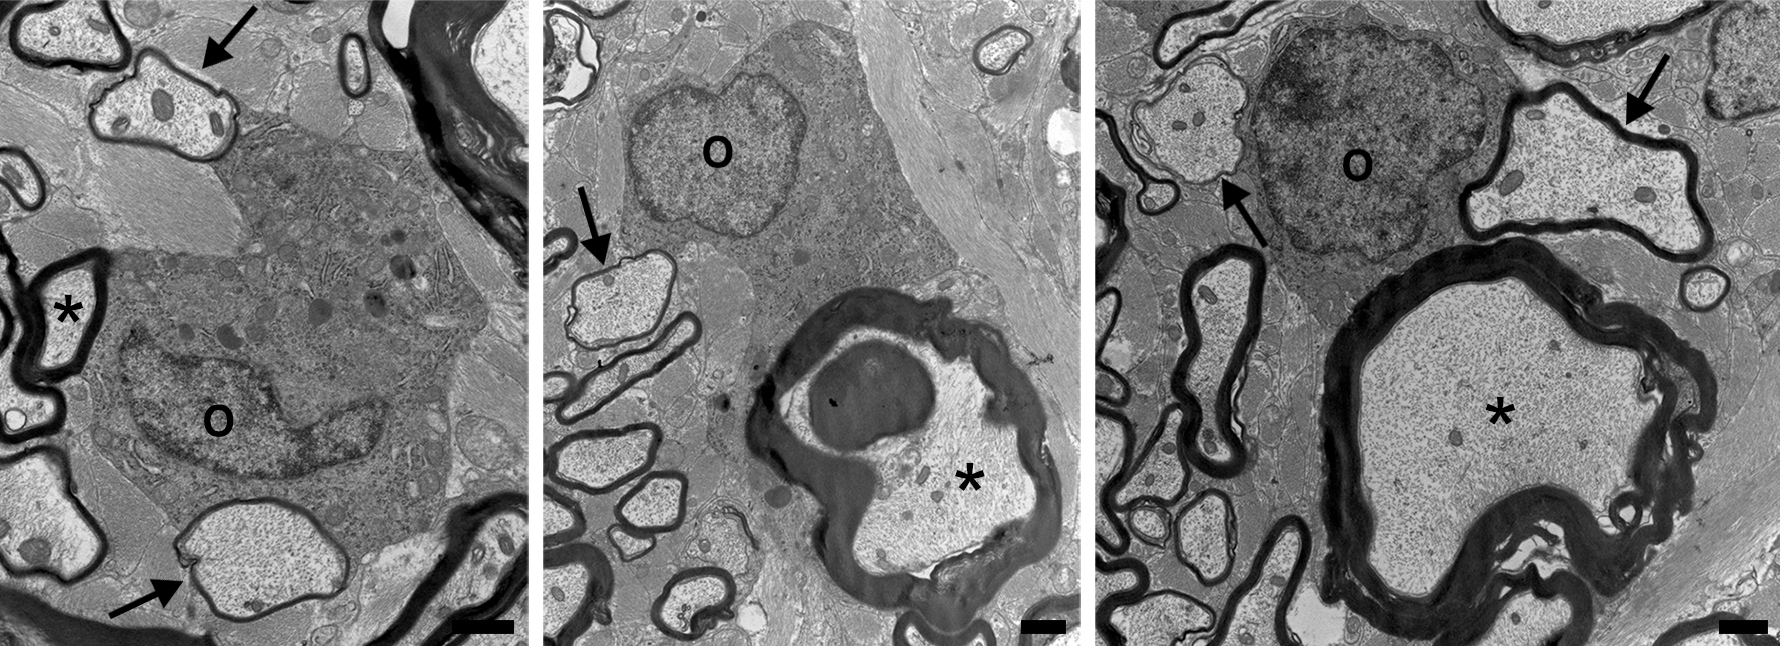

The UW–Madison researchers enlisted Grahame Kidd and the private research lab Renovo Neural in Cleveland to reconstruct stacks of electron microscope images of cat nerve cells into 3D representations that show oligodendrocytes reaching up and down the spinal cord, sustaining mature myelin and remyelinating damaged sheaths.

In the new study, the researchers looked at the cats’ nervous tissue and found a unique myelin mosaic — axons surrounded by thick layers of myelin (formed during development when the axons themselves grew) were interspersed with other axons surrounded by thin layers of myelin.

“The most likely explanation of that mosaic appearance is surviving oligos,” Duncan says. “Thick myelin sheaths are never seen following remyelination, just thin sheaths. And surviving adult oligodendrocytes are adjacent to these sites of demyelination, making them likely candidates for myelin repair.”

Sure enough, the researchers found oligodendrocytes connected to both thick and thin myelin sheaths in the cat spinal cord.

“You see in the monkeys, too, single oligodendrocytes connected to mature myelin sheaths that also have processes extended out to and surrounding demyelinated axons,” Duncan says.